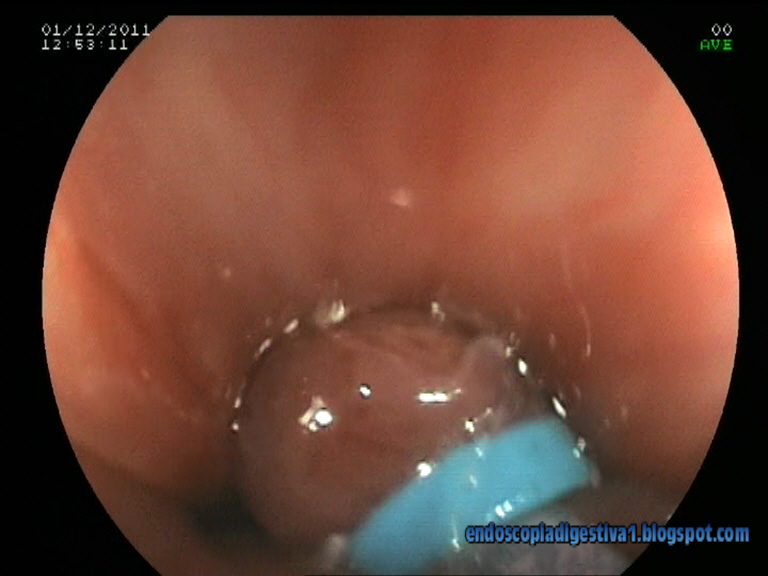

Paciente varón de 78 años de edad con antecedentes de HTA, hiperlipemia, esófago de Barrett corto de > 7 años de evolución (controles endoscópicos anuales con metaplasia intestinal, aunque displasia leve en una de las muestras de la gastroscopia realizada a finales de 2010) y cáncer de colon sincrónico (recto, colon descendente y colon ascendente) intervenido en octubre del presente año (colectomia subtotal; estadiaje T3-N0-M0) . En la gastroscopia de control del esófago de Barrett realizada en agosto, se advierte una nodulación de 3 mm con ligera depresión central justo por encima de la unión GE que histológicamente se define como una displasia severa-carcinoma in situ. Se decide realizar mucosectomía de la lesión con bandas elásticas y resección por debajo de ésta que cursa sin complicaciones inmediatas. El estudio histológico de la pieza confirma la histología descrita, no apreciandose datos de adenocarcinoma microinvasor (T2). La idea final es aplicar una técnica de ablación con radiofrecuencia tipo HALO 360º para completar el tratamiento de la mucosa con epitelio de Barrett.

El esófago de Barrett con displasia severa o carcinoma intramucoso es suceptible de un tratamiento endoscópico con intención curativa. Sin duda, la mejor técnica es la disección endoscópica submucosa (ESD), pero es compleja, con una tasa de complicaciones no desdeñable y está muy poco extendida en Occidente. La mucosectomìa endoscópica es una alternativa bastante mas sencilla, con % de complicaciones menor, que si ha tenido aceptación en los paises occidentales. Los dos métodos mas difundidas son el sistema de bandas Duette (Cook) y el de Caps sin ligadura (Olympus). El primero es algo mas sencillo ya que es muy similar a la ligadura de varices con bandas. Se exponen dos ejemplos de las técnicas descritas del DAVE Project:

En nuestro centro estamos en espera de disponer de alguno de estos 2 métodos. Mientras tanto hemos optado por una alternativa mas barata usando el sistema de bandas elásticas (Speedband 7) de Boston Scientific en base al ejemplo que Max Yoza expone en su blog de endoscopia digestiva ENDOTUBE (http://www.endotube.blogspot.com/2010/10/mucosectomia-en-esofago-de-barrett-con.html). Está claro que es mas engorroso porque obliga a introducir un endoscopio cada vez que se va a resecar una banda, pero te saca del apuro.